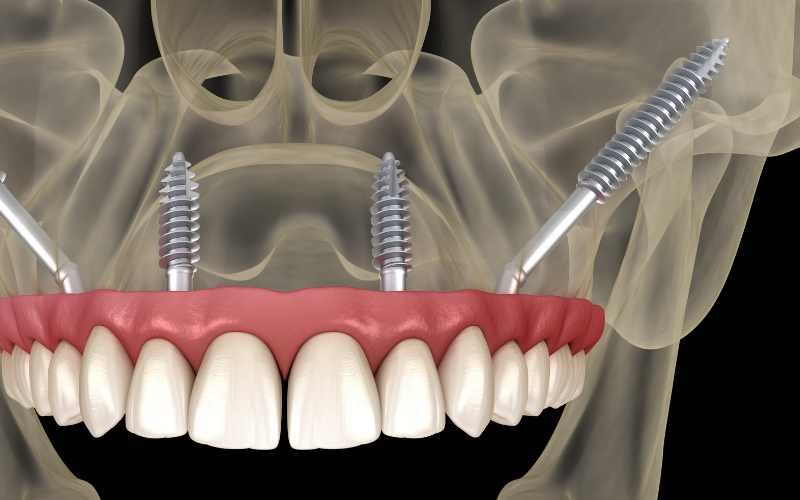

שתלי זיגומה הם שתלים ארוכים במיוחד (30-55 מ"מ) המעוגנים בעצם הזיגומטית (עצם הלחי). הם מהווים פתרון מתקדם למקרים של חוסר עצם חמור בלסת העליונה, כאשר אין מספיק עצם להתקנת שתלים רגילים גם לאחר הרמת סינוס.

יתרונות:

שיקולים קליניים: